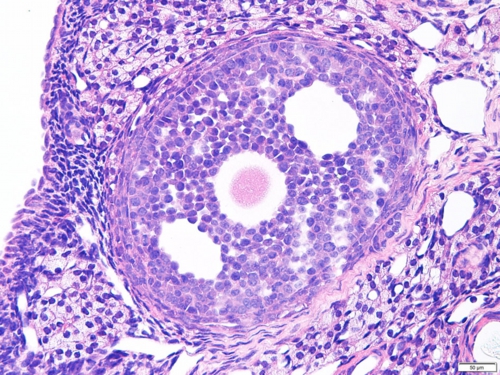

卵巣(ラット) Ovary ( rat )

厚さ5 µm パラフィン切片のヘマトキシリン・エオジン染色光学顕微鏡画像

Light microscopic image of 5 µm-thin paraffin section with hematoxylin & eosin staining

成熟が進む卵胞の中心部には大きな卵母細胞が観察されます。